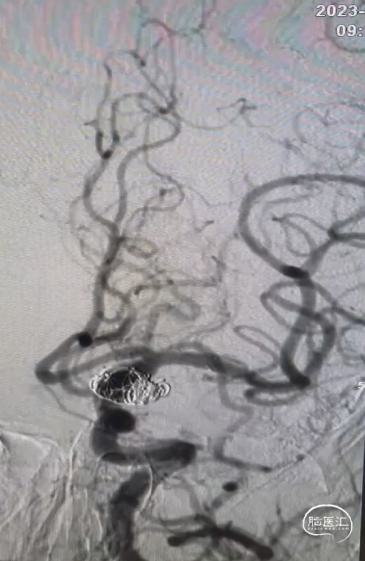

术前造影

CTA提示:右侧大脑中动脉动脉瘤。

造影提示:动脉瘤瘤颈累及上下干支,下干支与M1成角较锐S弯;患者右侧颈内动脉非常迂曲。

3D造影成像:动脉瘤大小约3.7*3.1mm。

其它颅内血管未见异常。